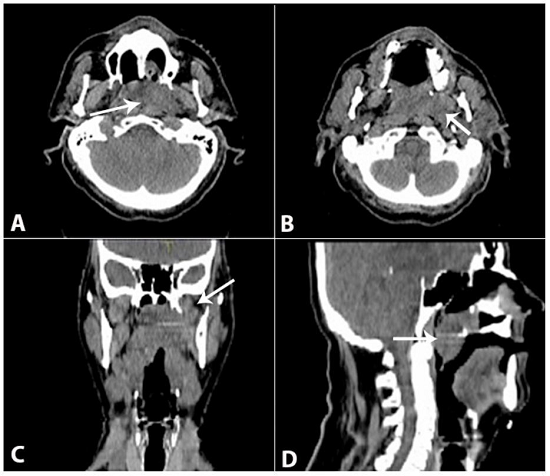

The patient was treated with primary chemotherapy with carboplatin AUC5 (day 1) and etoposide 100 mg/m2 (days 1, 2, and 3) every 21 days. After the end of the fourth cycle of chemotherapy, the patient underwent a planning CT scan (Figure 2) and started radiotherapy receiving a total dose of 70 Gy to the nasopharynx and 60 Gy to the cervical region.